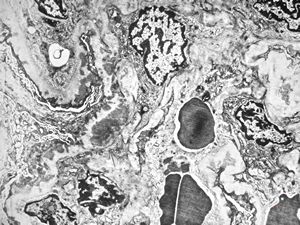

M,22y. | type II membranoproliferative glomerulonephritis